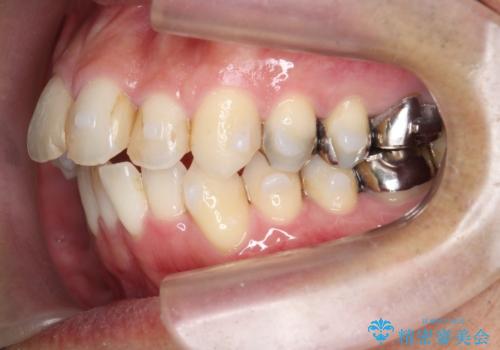

矯正と虫歯のセラミック治療 総合歯科治療の実践

- 突き出た前歯の角度の改善と虫歯治療の改善を求めて来院されました。

虫歯を除去したのち、マウスピース矯正治療を行い、歯並びやがたつきを改善したのち、セラミックに置き換えることで審美性の向上を計画します。